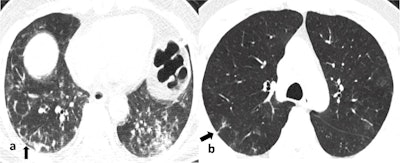

Ground-glass opacity (GGO) was the dominant abnormality found in all 51 cases. Pure GGO was observed in 15 (29%), GGO with crazy-paving pattern was seen in 15 (29%), and GGO mixed with consolidation was noted in 21(41%). Perilesional or intralesional segmental or subsegmental pulmonary vessel enlargement was observed in 36 (71%) of cases.

"Most of the findings we observed were in tune with the published data, however, low prevalence of chest CT findings in our population was intriguing," they reported. "Secondly, segmental pulmonary vessel enlargement was a unique finding in COVID-19 pneumonia that we observed in our cohort. This finding is peculiar to COVID-19 pneumonia and has a diagnostic value."